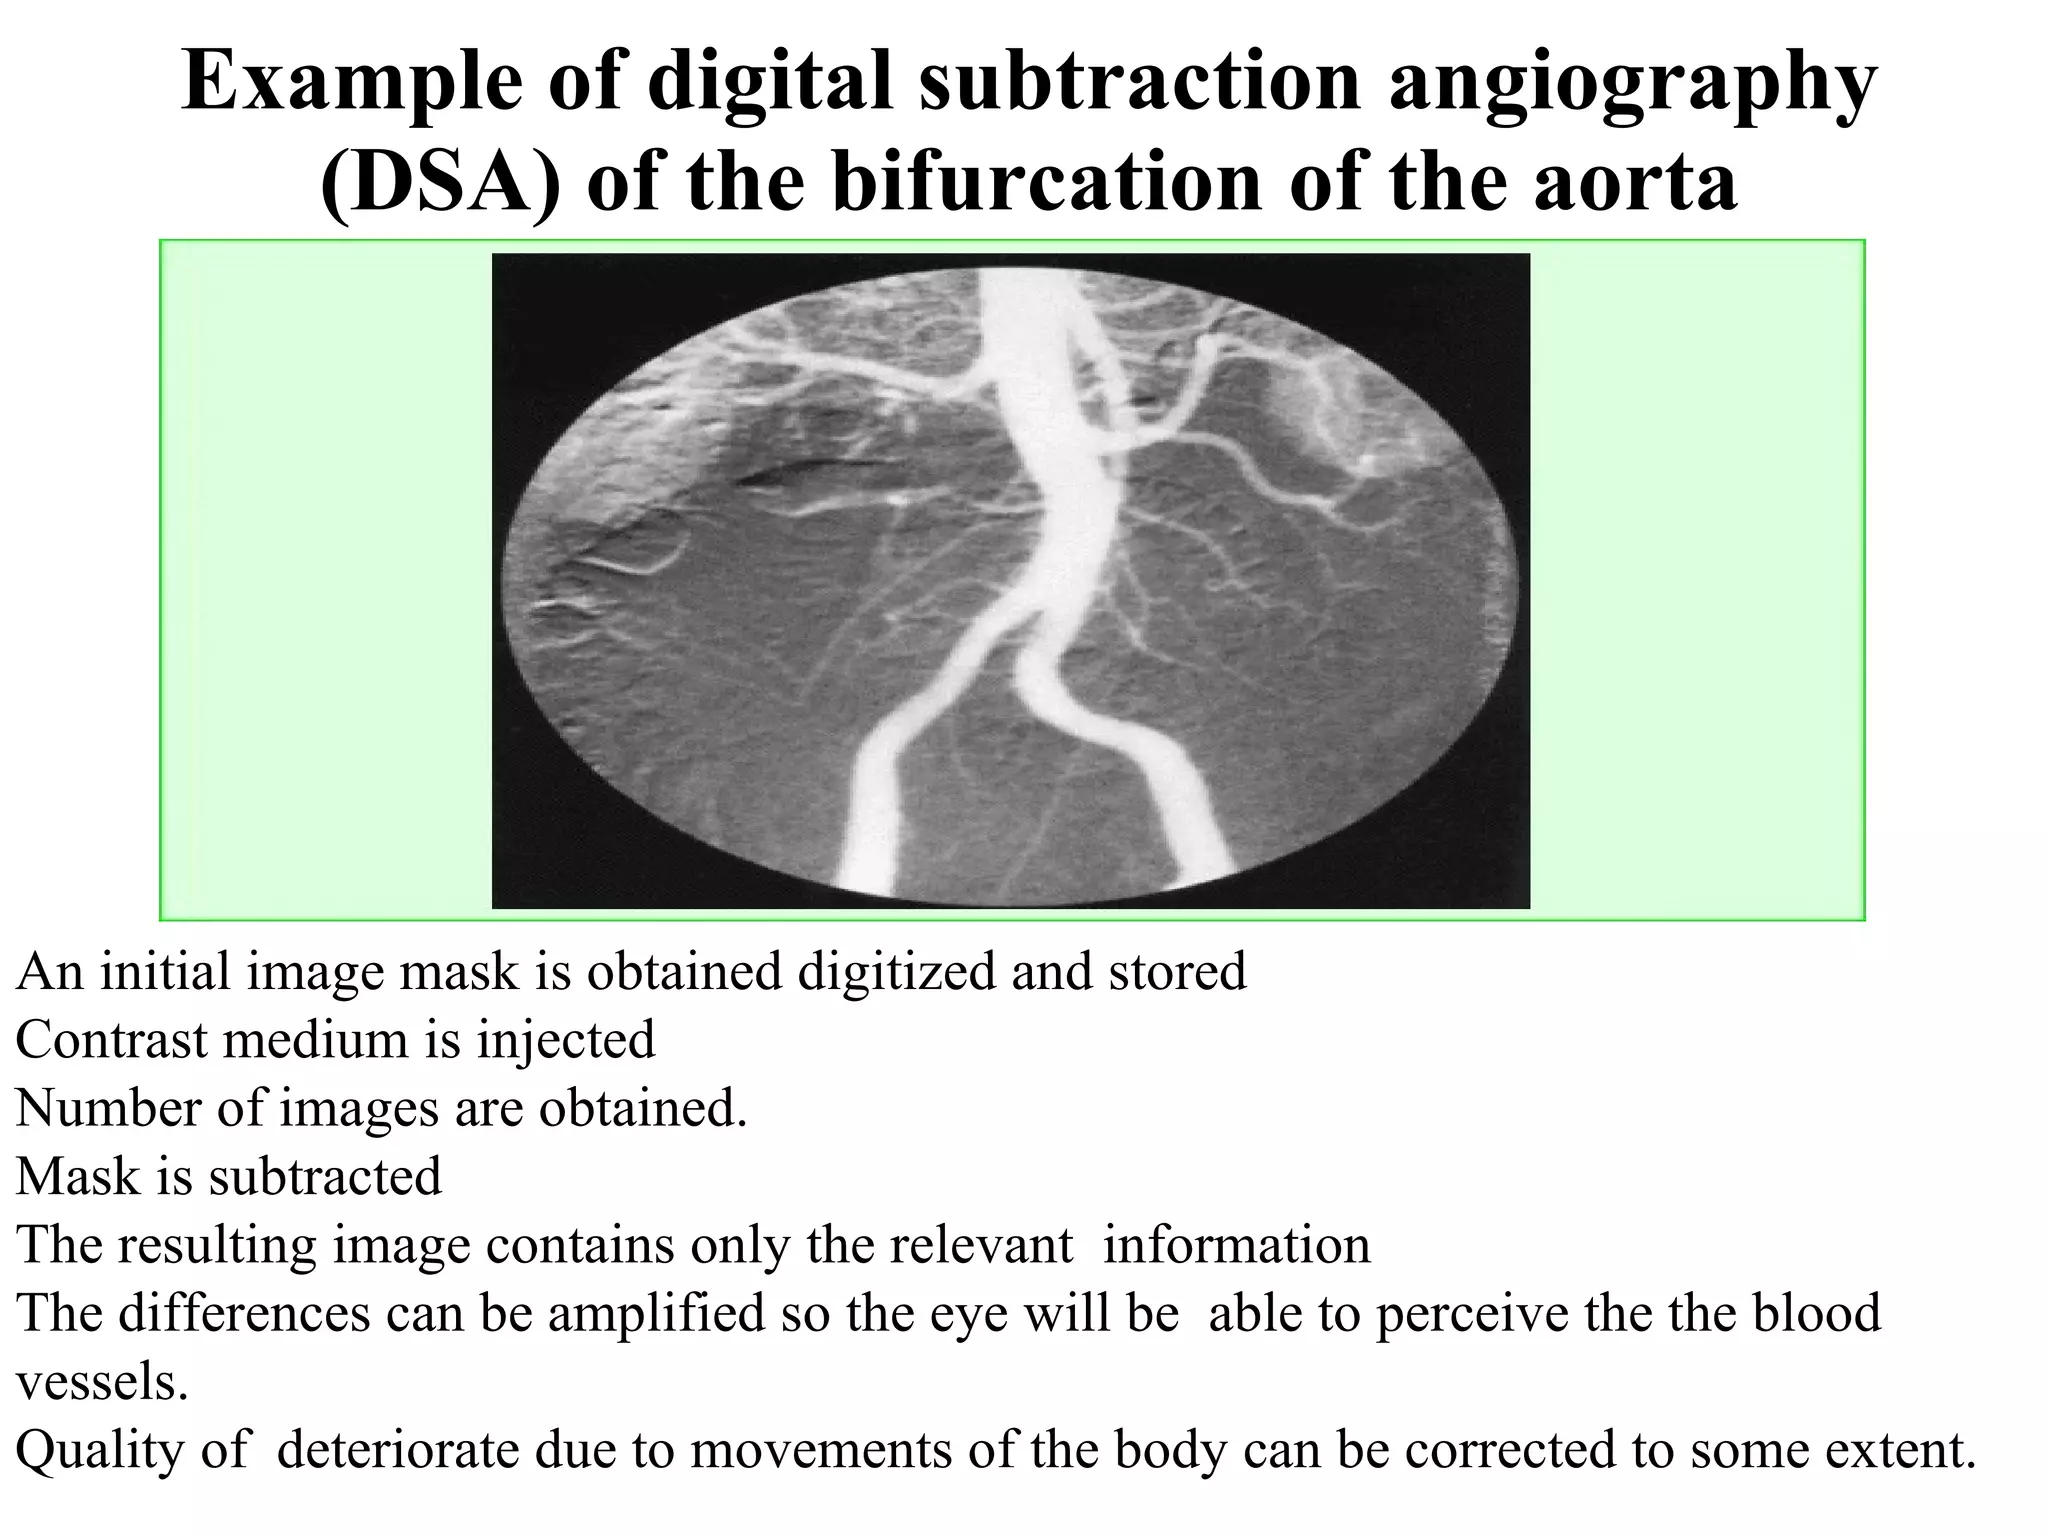

The document discusses various medical imaging modalities including x-rays, computed tomography (CT), and digital mammography. It describes the basic principles and historical development of these technologies, how images are formed, and what types of anatomical features and abnormalities they can detect. Key advances include the development of digital systems that allow image manipulation and remote consultation. While promising, digital mammography still faces challenges around resolution and cost.